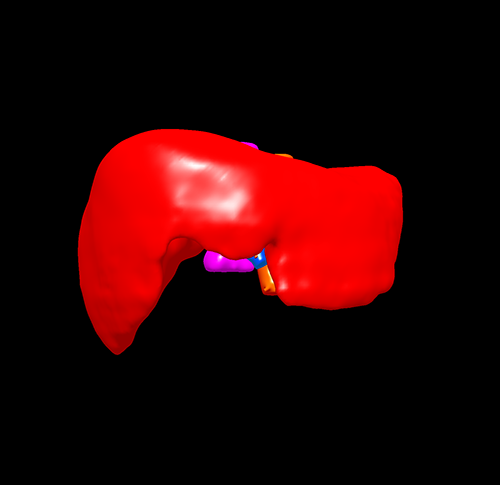

S678肝癌 ---腹腔镜右半肝切除